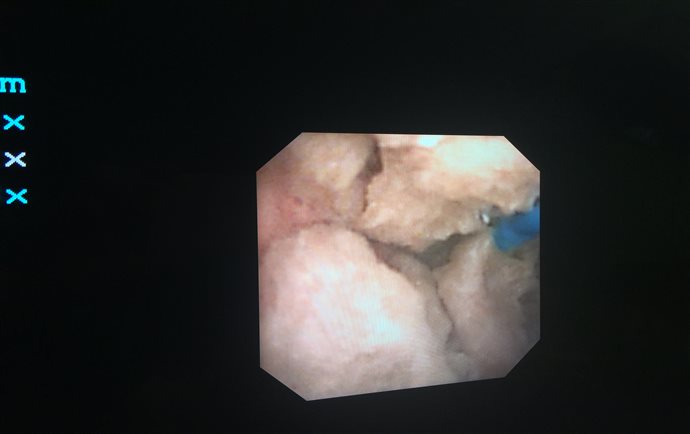

经尿道前列腺增生等离子电切及前列腺激光剜除术

前列腺增生是老年男性的常见病。主要症状有进行性排尿困难,夜尿次数增多等;严重者可导致肾功能受损,甚至危及生命。目前国际上公认的前列腺增生诊疗的“金标准”是经尿道前列腺电切术(TURP)。通俗地讲,就是通过膀胱镜行前列腺切除的一种手术。其优点是手术创伤小(无切口),出血少,术后恢复快,疗效与开放手术相同。一般不需要输血,一般无手术并发症。我院于1996年起开展了这项微创手术,目前已经累计治疗5000余例病人,积累了丰富的临床经验。